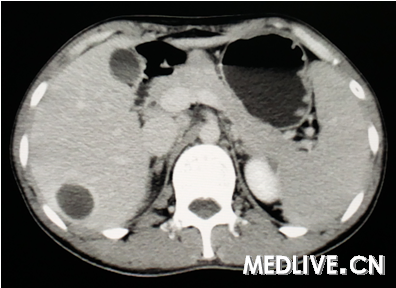

男,26岁,右上腹部疼痛伴畏寒发热3天。

图1为CT增强动脉期,

右上腹痛伴畏寒发热提示有感染存在,CT为囊性病变,动脉期囊腔周围有水肿,静脉期囊腔边缘增强,囊内无增强排除血管瘤;囊内无子囊,无分隔可排除肝包虫感染。最终诊断为肝脓肿。

诊断:肝脓肿。 依据:发热,畏寒考虑感染性疾病,患者右上腹疼,上腹部CT肝右叶可见空腔,周围水肿带,增强可见强化,符合肝脓肿影像。 鉴别:肝囊肿并感染,肝结核。

上腹痛伴畏寒发热提示有感染存在,排除肝囊肿;CT示球形囊性病变,动脉期囊腔周围有水肿,静脉期囊腔边缘增强,囊内无增强排除血管瘤;囊内无子囊,无分隔可排除肝包虫感染。诊断考虑肝脓肿。

CT可见肝内囊性病变,边界清,囊内呈液性暗区(无增强),无分隔,囊腔周围有水肿,综合上述CT表现诊断为肝脓肿。